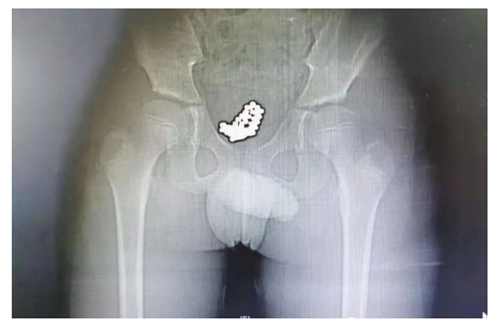

男孩名叫央奇(化名),今年10岁。因尿痛、血尿1天,于7月9日上午10点,由父母带领来到我院看急诊。医生询问病情时,发现小奇全程都低着头,好像试图躲避医生和家长的眼神,只说自己头天下午去游了泳,其他一概支支吾吾、避而不答。随后,医生给他拍了一个CT,一拿到片子就大致猜到是怎么回事了。“从片子可以清晰看到,他的膀胱里充满了一颗颗小珠子,直径大约5毫米 ,估计是不久前塞进去的!”泌尿外科副主任医师刘明分析。

患者的CT片